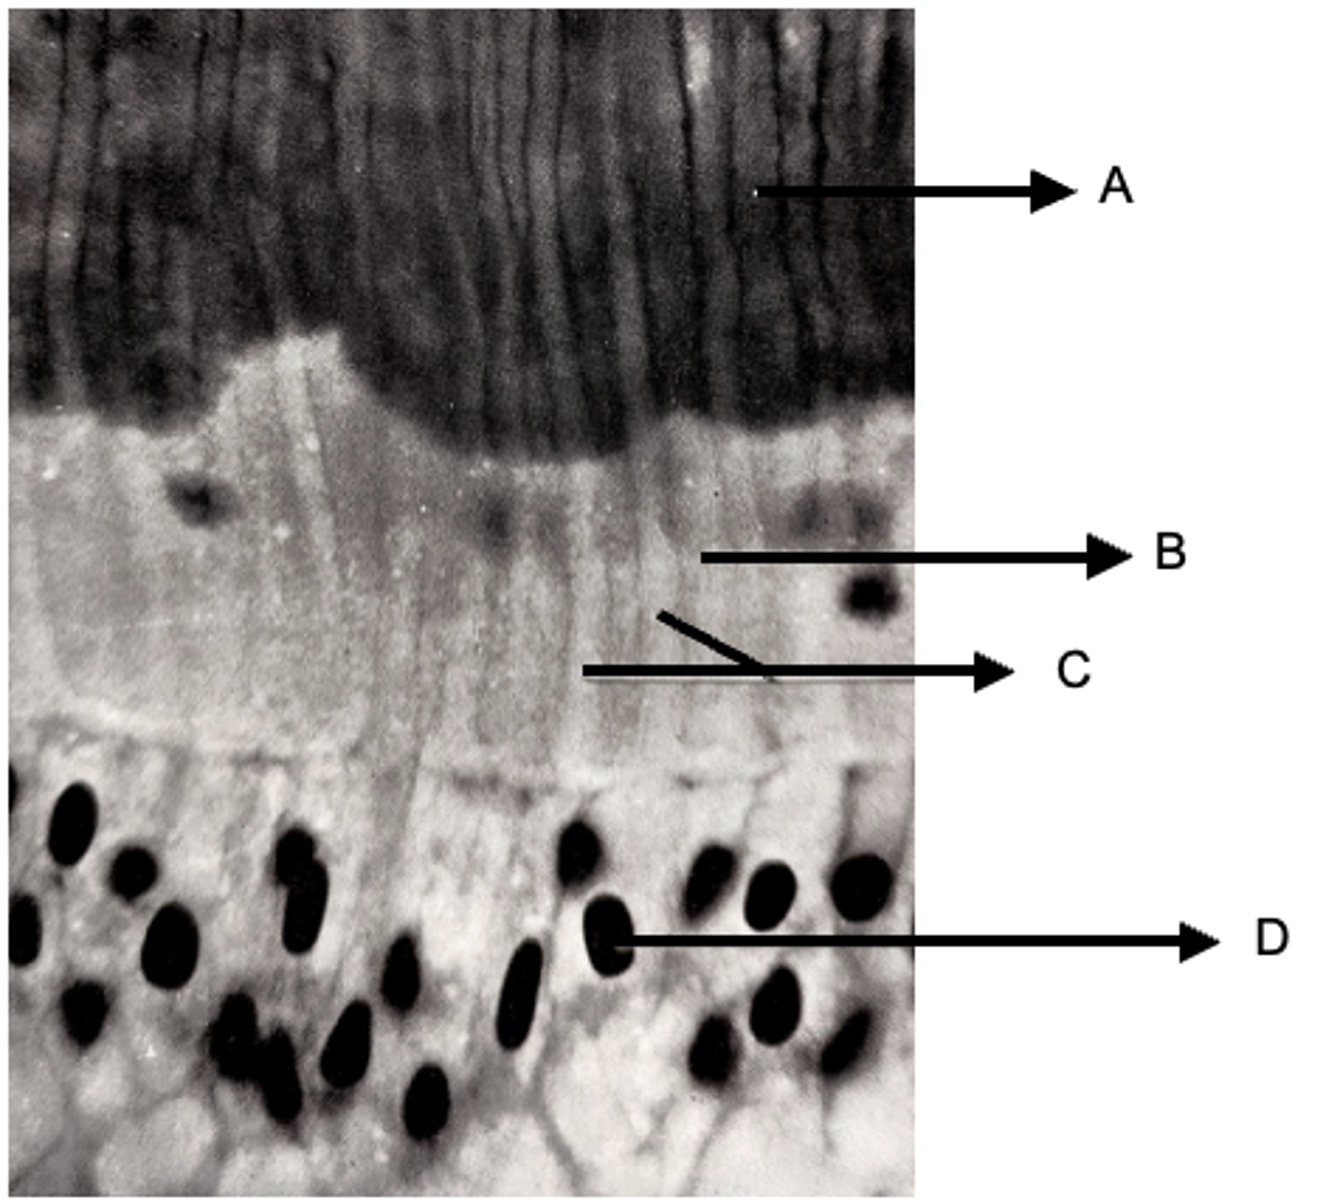

Label this image

A: Calcified dentin

B: Uncalcified dentin (predentin)

C: Odontoblastic processes

D: Bodies of odontoblasts